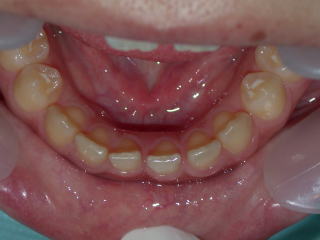

術前平成25年2月12日、いわゆるすきっ歯が気になるそうです。